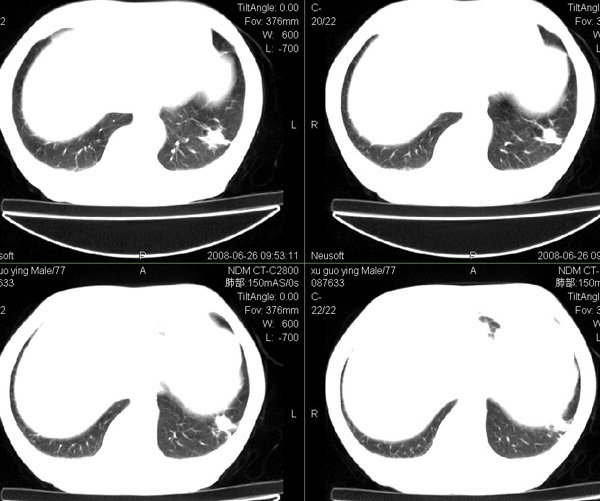

以下是引用狙击手在2008-6-26 20:16:00的发言:[br]上腹部除了胆囊大一点,其余未见明显异常,肺尖部见纤维条索样影,左肺下叶见空洞样占位,壁较厚,临近胸膜见牵拉,周围未见卫星灶,考虑:1:左下肺周围性肺癌;2:肺尖部陈旧性结合灶。

以下是引用liuqiang在2008-6-26 21:11:00的发言:[br]上腹部除了胆囊大一点,其余未见明显异常,肺尖部见纤维条索样影,左肺下叶见空洞样占位,壁较厚,临近胸膜见牵拉,周围未见卫星灶,考虑:1:左下肺周围性肺癌;2:肺尖部陈旧性j结核灶。